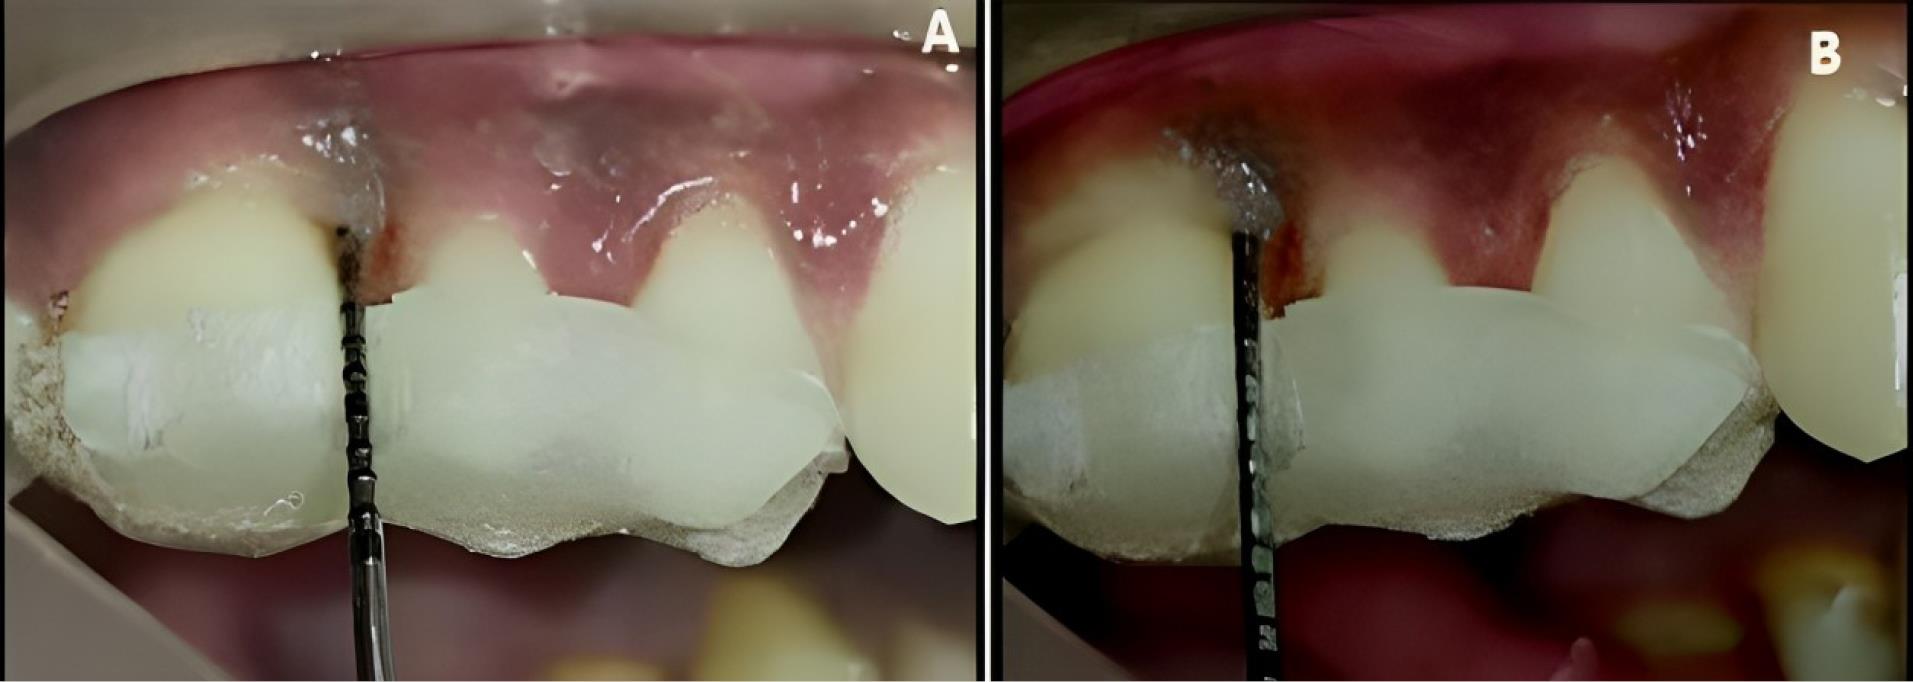

Patients were recalled and reviewed at the first, third, and sixth postoperative months, respectively, and correspondingly. All the clinical measurements were recorded at the third and sixth postoperative months, as shown in Figures 5 and 6, and the postoperative radiographs were taken at the end of six months, as shown in Figures 7 and 8.

Experimental site A, postoperative-clinical. A. 3 months. B. 6 months

Figure 5.

Figure 6.

Experimental site B, postoperative-clinical. A. 3 months. B. 6 months